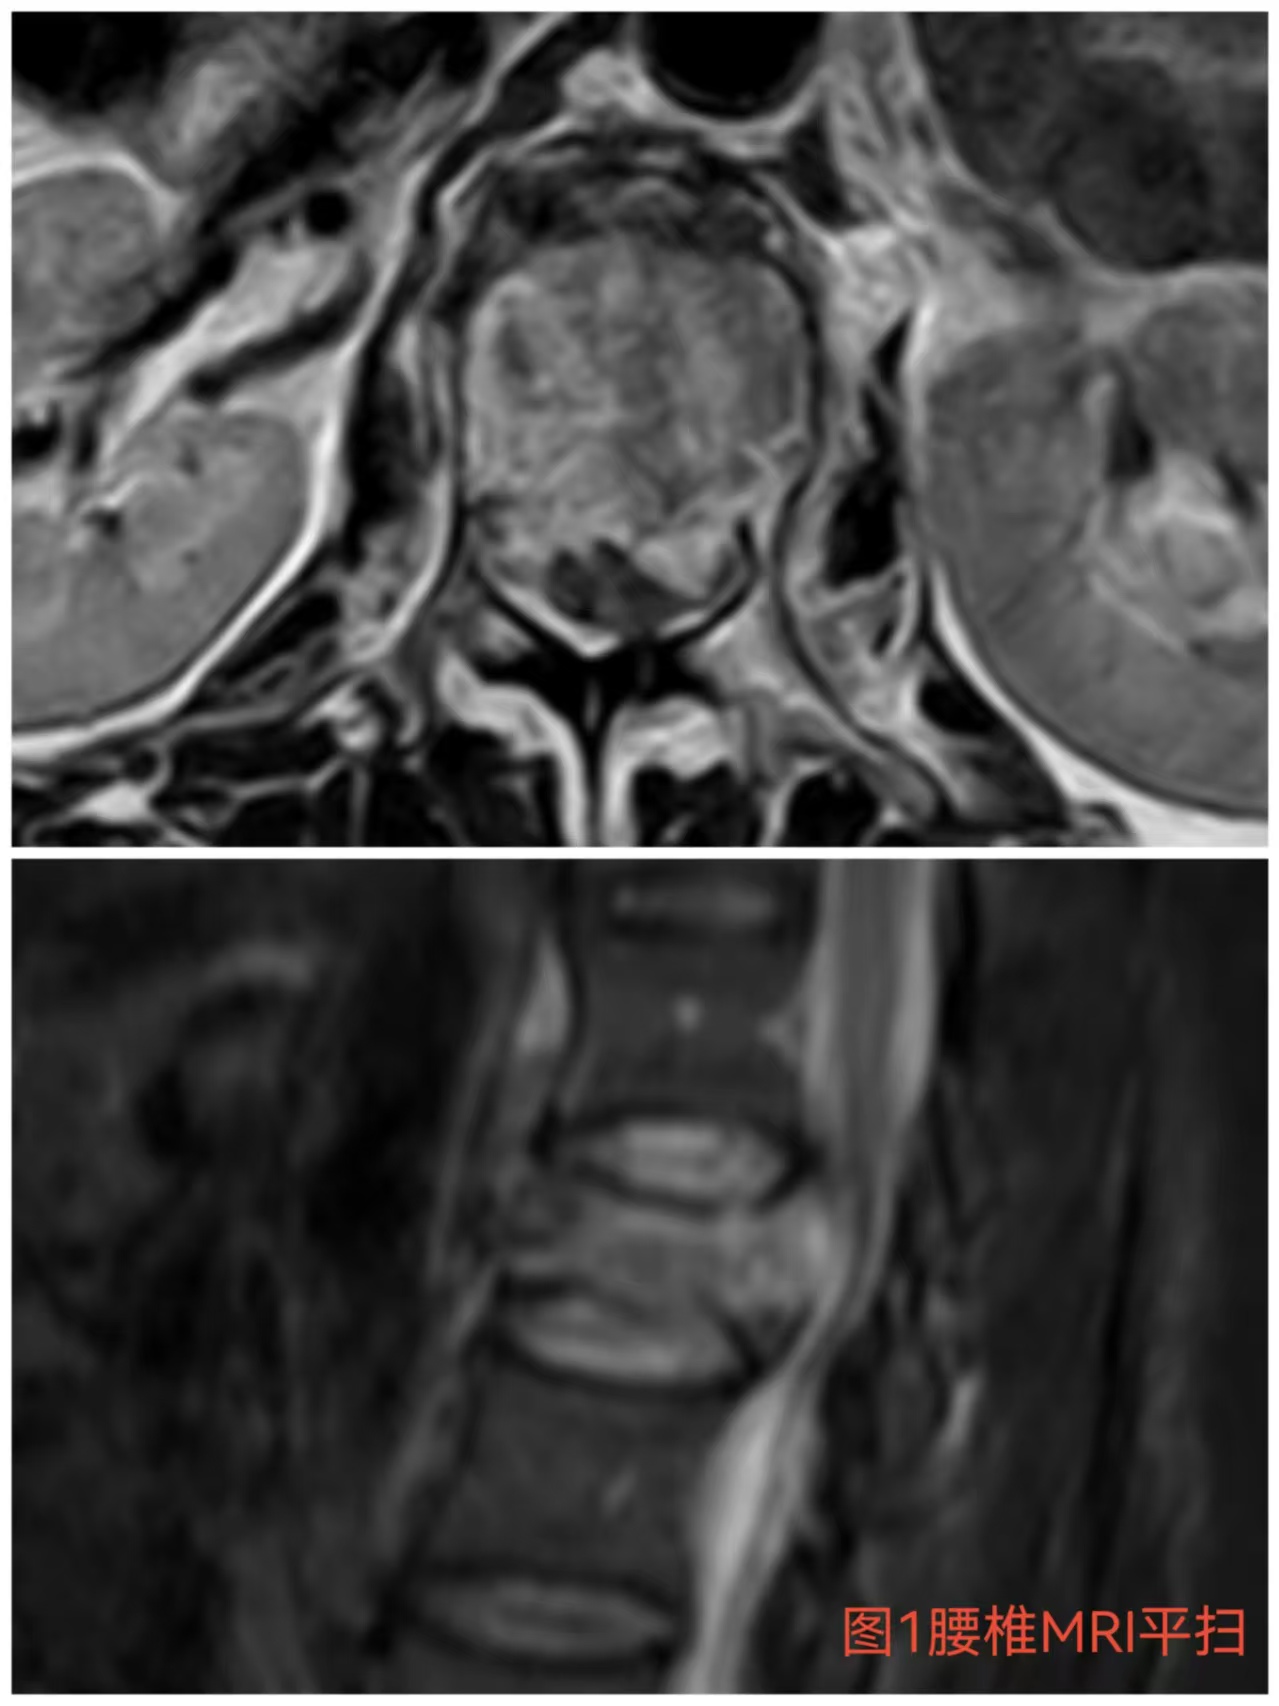

入院時患者躺在床上不能動彈,眼神中透漏著深深的無助,對于她來說這種傷情無疑是沉重的,尤其是腹股溝以下感覺消失、雙下肢肌力0級,這意味著其下肢無法活動及站立,仿佛被命運按下了暫停鍵;與病人及家屬充分溝通病情后,第一時間給予對癥治療,監測患者生命體征,行腰椎核磁檢查(圖1)提示:腰1椎體爆裂性骨折,椎體后緣塌陷致骨性椎管狹窄,壓迫脊髓神經,結合患者病情及輔助檢查可診斷為:“L1椎體爆裂性骨折伴雙下肢截癱”。